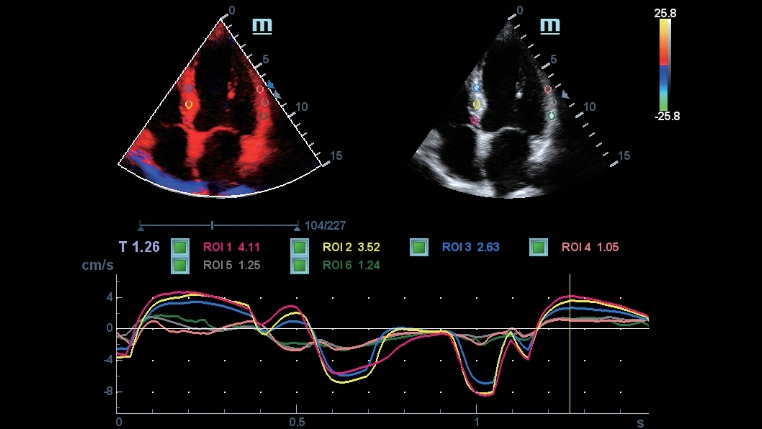

Gamma completa di strumenti: precisione garantita e praticitĂ

DC-40 con Full HD offre una gamma di strumenti in grado di massimizzare l'accuratezza diagnostica con praticitĂ . DC-40 con Full HD puĂČ essere utilizzato in diagnostica per immagini generale, ginecologia/ostetricia e cardiologia e costituisce una soluzione completa per le applicazioni cliniche tradizionali, con un flusso di lavoro semplificato per il massimo dell'efficienza.